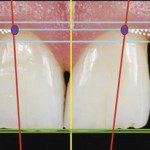

A figura 4 exibe a análise dental, a fotografia intraoral com o traçado das linhas de referências horizontais baseadas na linha interpupilar (linhas azuis: zênites gengivais; linhas verdes: bordas incisais) e verticais baseada na linha glabela/mento (linha amarela). É importante observar que os zênites gengivais dos incisivos centrais e laterais se apresentam no mesmo plano, mas o mesmo não observamos nos caninos, sendo o zênite gengival do direito significativamente mais alto. As linhas verdes indicam uma desarmonia significativa entre os incisivos laterais e principalmente entre os caninos. A linha média facial não se mostra coincidente com o ponto de contato entre os incisivos centrais, mostrando um desvio à direita. Os longos eixos dentários (linhas vermelhas) apresentam-se harmônicos, convergentes para a linha sagital mediana. Os zênites gengivais (pontos roxos) têm contorno ascendente de incisivos centrais para caninos. Traçada uma linha imaginária entre o zênite gengival do incisivo central e o zênite do canino, o zênite do incisivo lateral deve se situar nesta linha ou abaixo da mesma para proporcionar harmonia no sorriso, o que observamos no caso clínico.